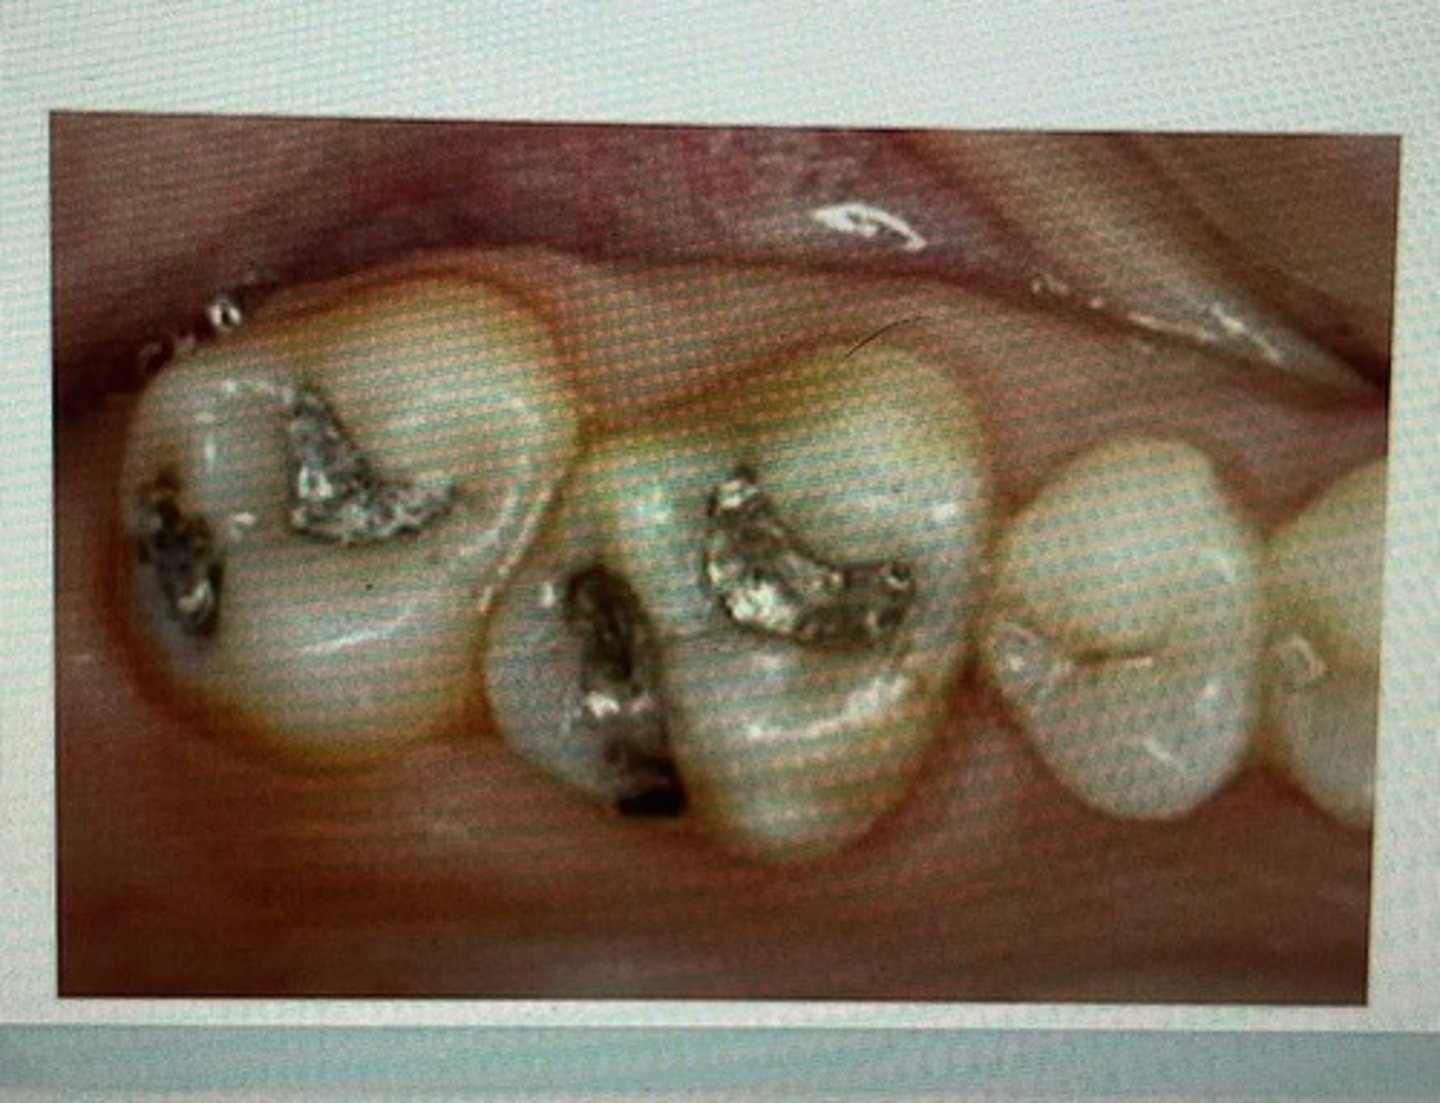

class I restoration